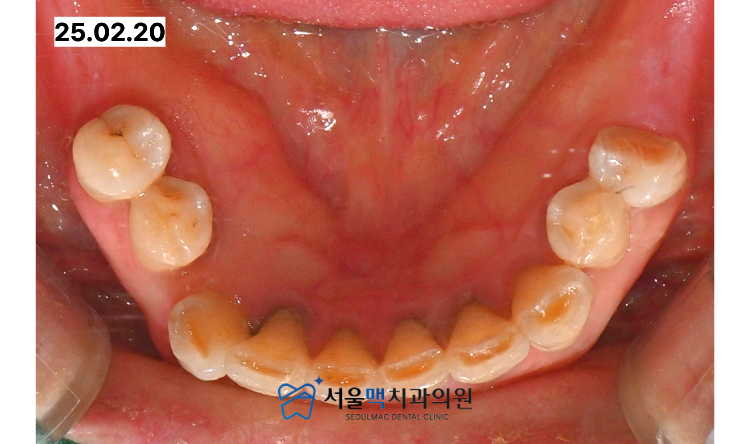

가양역치과 서울맥치과에 내원하신 이번 환자분은

상악의 앞니를 포함한 다수의 치아와

하악의 어금니 부위를 모두 상실하여

정상적인 식사가 불가능한 상태였습니다.

환자분의 구강 내를 면밀히 진찰한 결과

치아가 없는 상태로 오랜 시간이 흐르면서

상하악 사이의 수직적인 공간이

거의 소실된 상태였습니다.

특히 상악 전치부의 치아가 상실된 부위의

잇몸이 하악 치아와 거의 맞닿기

직전일 정도로 심하게 낮아져 있었습니다.